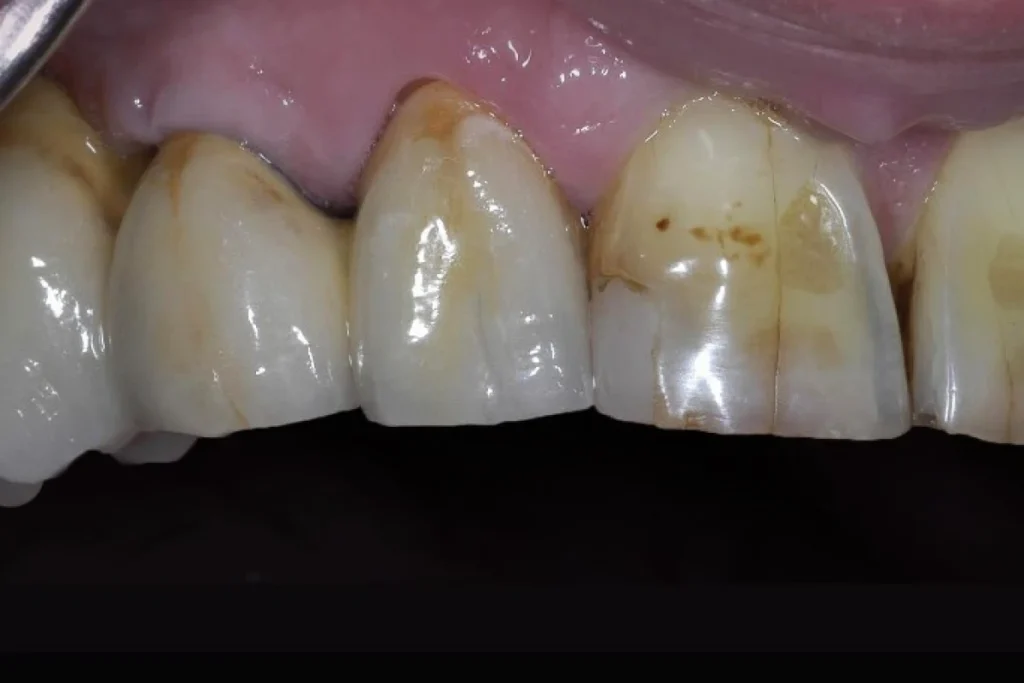

1. Les couronnes dentaires

La couronne est probablement la restauration conjointe la plus répandue. Elle recouvre et protège une dent fragilisée, lui redonne sa forme anatomique et restaure sa fonction masticatoire. Elle est indiquée lorsqu’une dent a été dévitalisée, fracturée, fragilisée par une carie profonde ou simplement trop altérée pour supporter une restauration plus simple.

Différents matériaux peuvent être utilisés dans la fabrication des couronnes :

- Céramique : elle offre un rendu esthétique naturel et se rapproche au plus près de la dent d’origine.

- Zircone : elle combine solidité, fiabilité et esthétique, et convient parfaitement aux zones visibles.

- Métallo-céramique : composée d’une armature métallique recouverte de céramique, elle représente un excellent compromis entre résistance et esthétique.

- Alliages précieux (exemple : or) : particulièrement durables, ils sont utilisés dans certaines situations spécifiques.

Le choix du matériau dépend à la fois du contexte clinique, des attentes du praticien et des souhaits du patient.